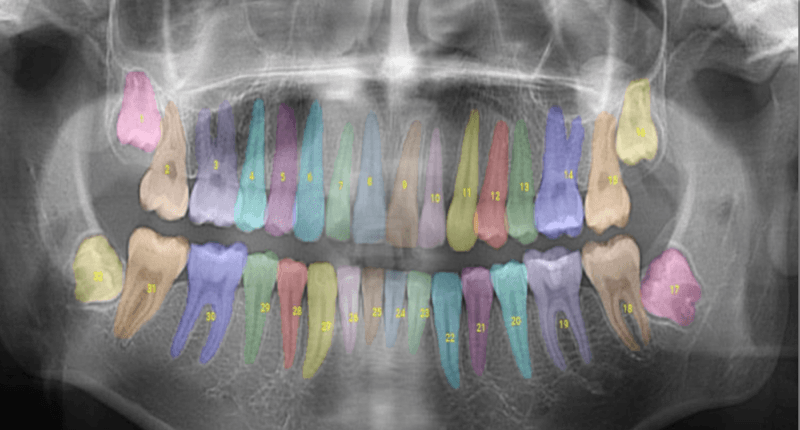

OverjetのFDA認証済みAIは、X線をリアルタイムで解析して注釈を付け、虫歯の輪郭を描き、骨量を定量化し、色や寸法を追加して、臨床チームと患者の両方がどこに注目すべきかを把握できるようにするものです。